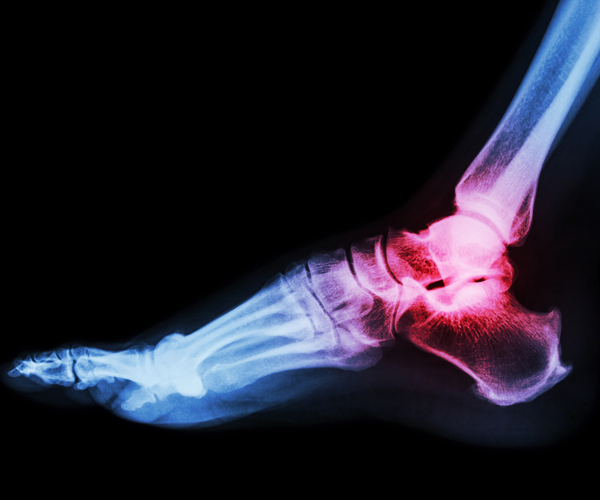

Specifically, she explained, that capability exists in a “gradient.” It’s greatest in the ankle, less apparent in the knee, and lowest in the hip.

For one, he said, could this be a partial explanation for why osteoarthritis is common in the knees and hips, but not the ankles?